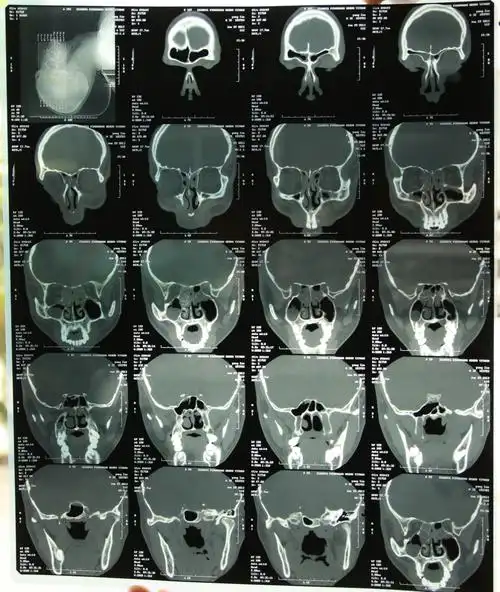

鼻子骨折的x光片